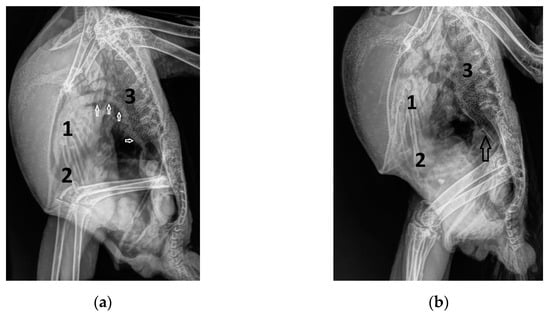

Figure 1.

Laterolateral radiographs of Congo grey parrots with atherosclerosis: (a) with a hyperdense aorta without calcifications (arrow) and a normal heart silhouette (GP from group 2); (b) with a hyperdense aorta with calcifications (arrow) and a normal heart silhouette (GP from group 1); (c,d) with hyperdense aorta with varying degrees of calcifications (arrow) and signs of heart failure, such as an enlarged heart silhouette, lung edema, and an enlarged liver silhouette due to effusion into the hepatoperitoneal cavity (GP from group 3); 1: heart silhouette; 2: liver; 3: lungs.